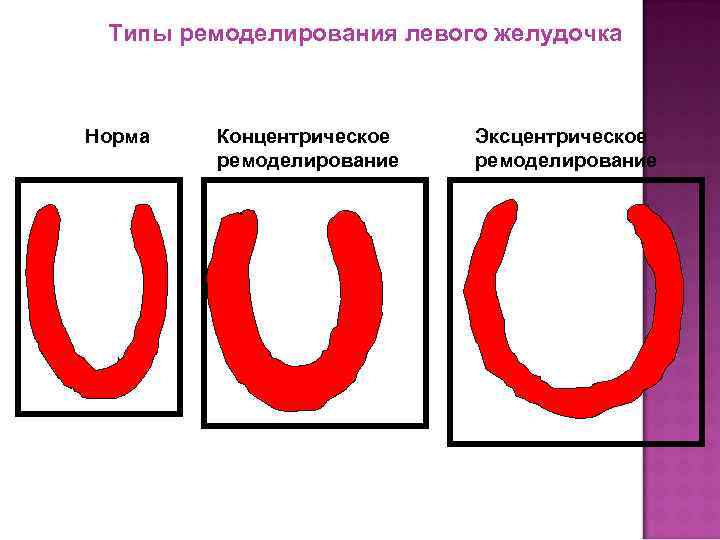

Типы ремоделирования левого желудочка Норма Концентрическое ремоделирование Эксцентрическое ремоделирование

Типы ремоделирования левого желудочка Норма Концентрическое ремоделирование Эксцентрическое ремоделирование